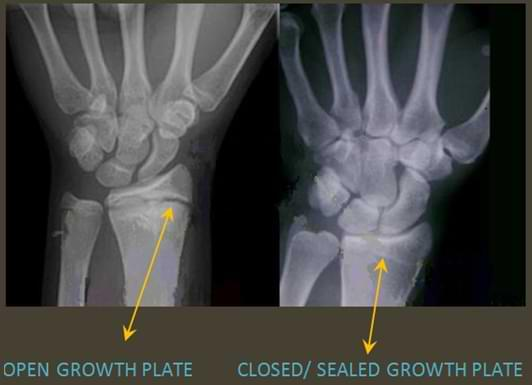

how to know if the growth plates are closed?

Most people get an x-ray of their hand and wrist.

From this they can determine not only whether your plates are open/closed, but your bone age too.